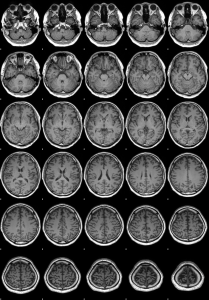

FSLを用いたシェルスクリプト演習:脳3次元T1強調MRIの水平断